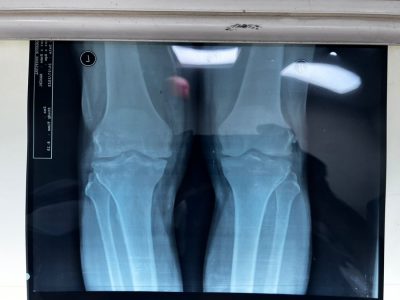

تدريسي في كلية طب المستنصرية يجري عملية تبديل مفصلي الركبتين لمريض في مستشفى اليرموك التعليمي

وقال رئيس الفريق الطبي الدكتور محمد جعفر الموسوي : أن المريض كان يعاني من عدم القدرة عل الحركة نتيجة سوفان متقدم في مفصلي الركبتين الأيمن والأيسر ، وبعد اجراء الفحوصات السريرية والمختبرية والشعاعية أجريت له عملية تبديل مفصلي الركبتين ولله الحمد استطاع المريض السير في اليوم الأول بعد العملية.